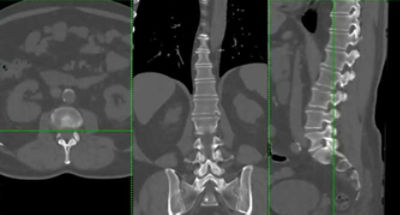

Ct Lumbar Spine Protocol Radiology Reference Article Radiopaedia Org